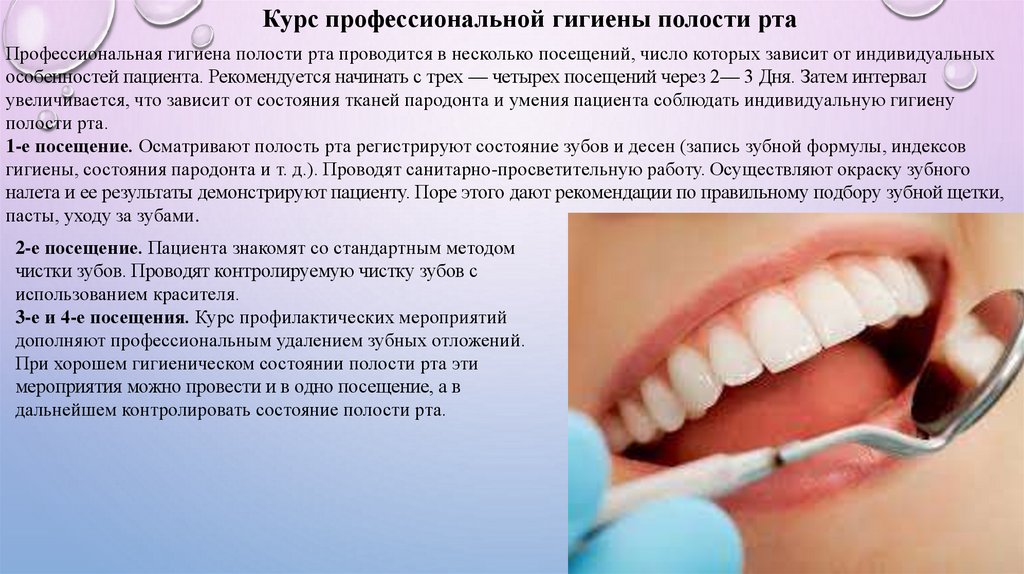

Этапы чистки зубов: Правильный уход за полостью рта

Раздел: Снимки-подсказки